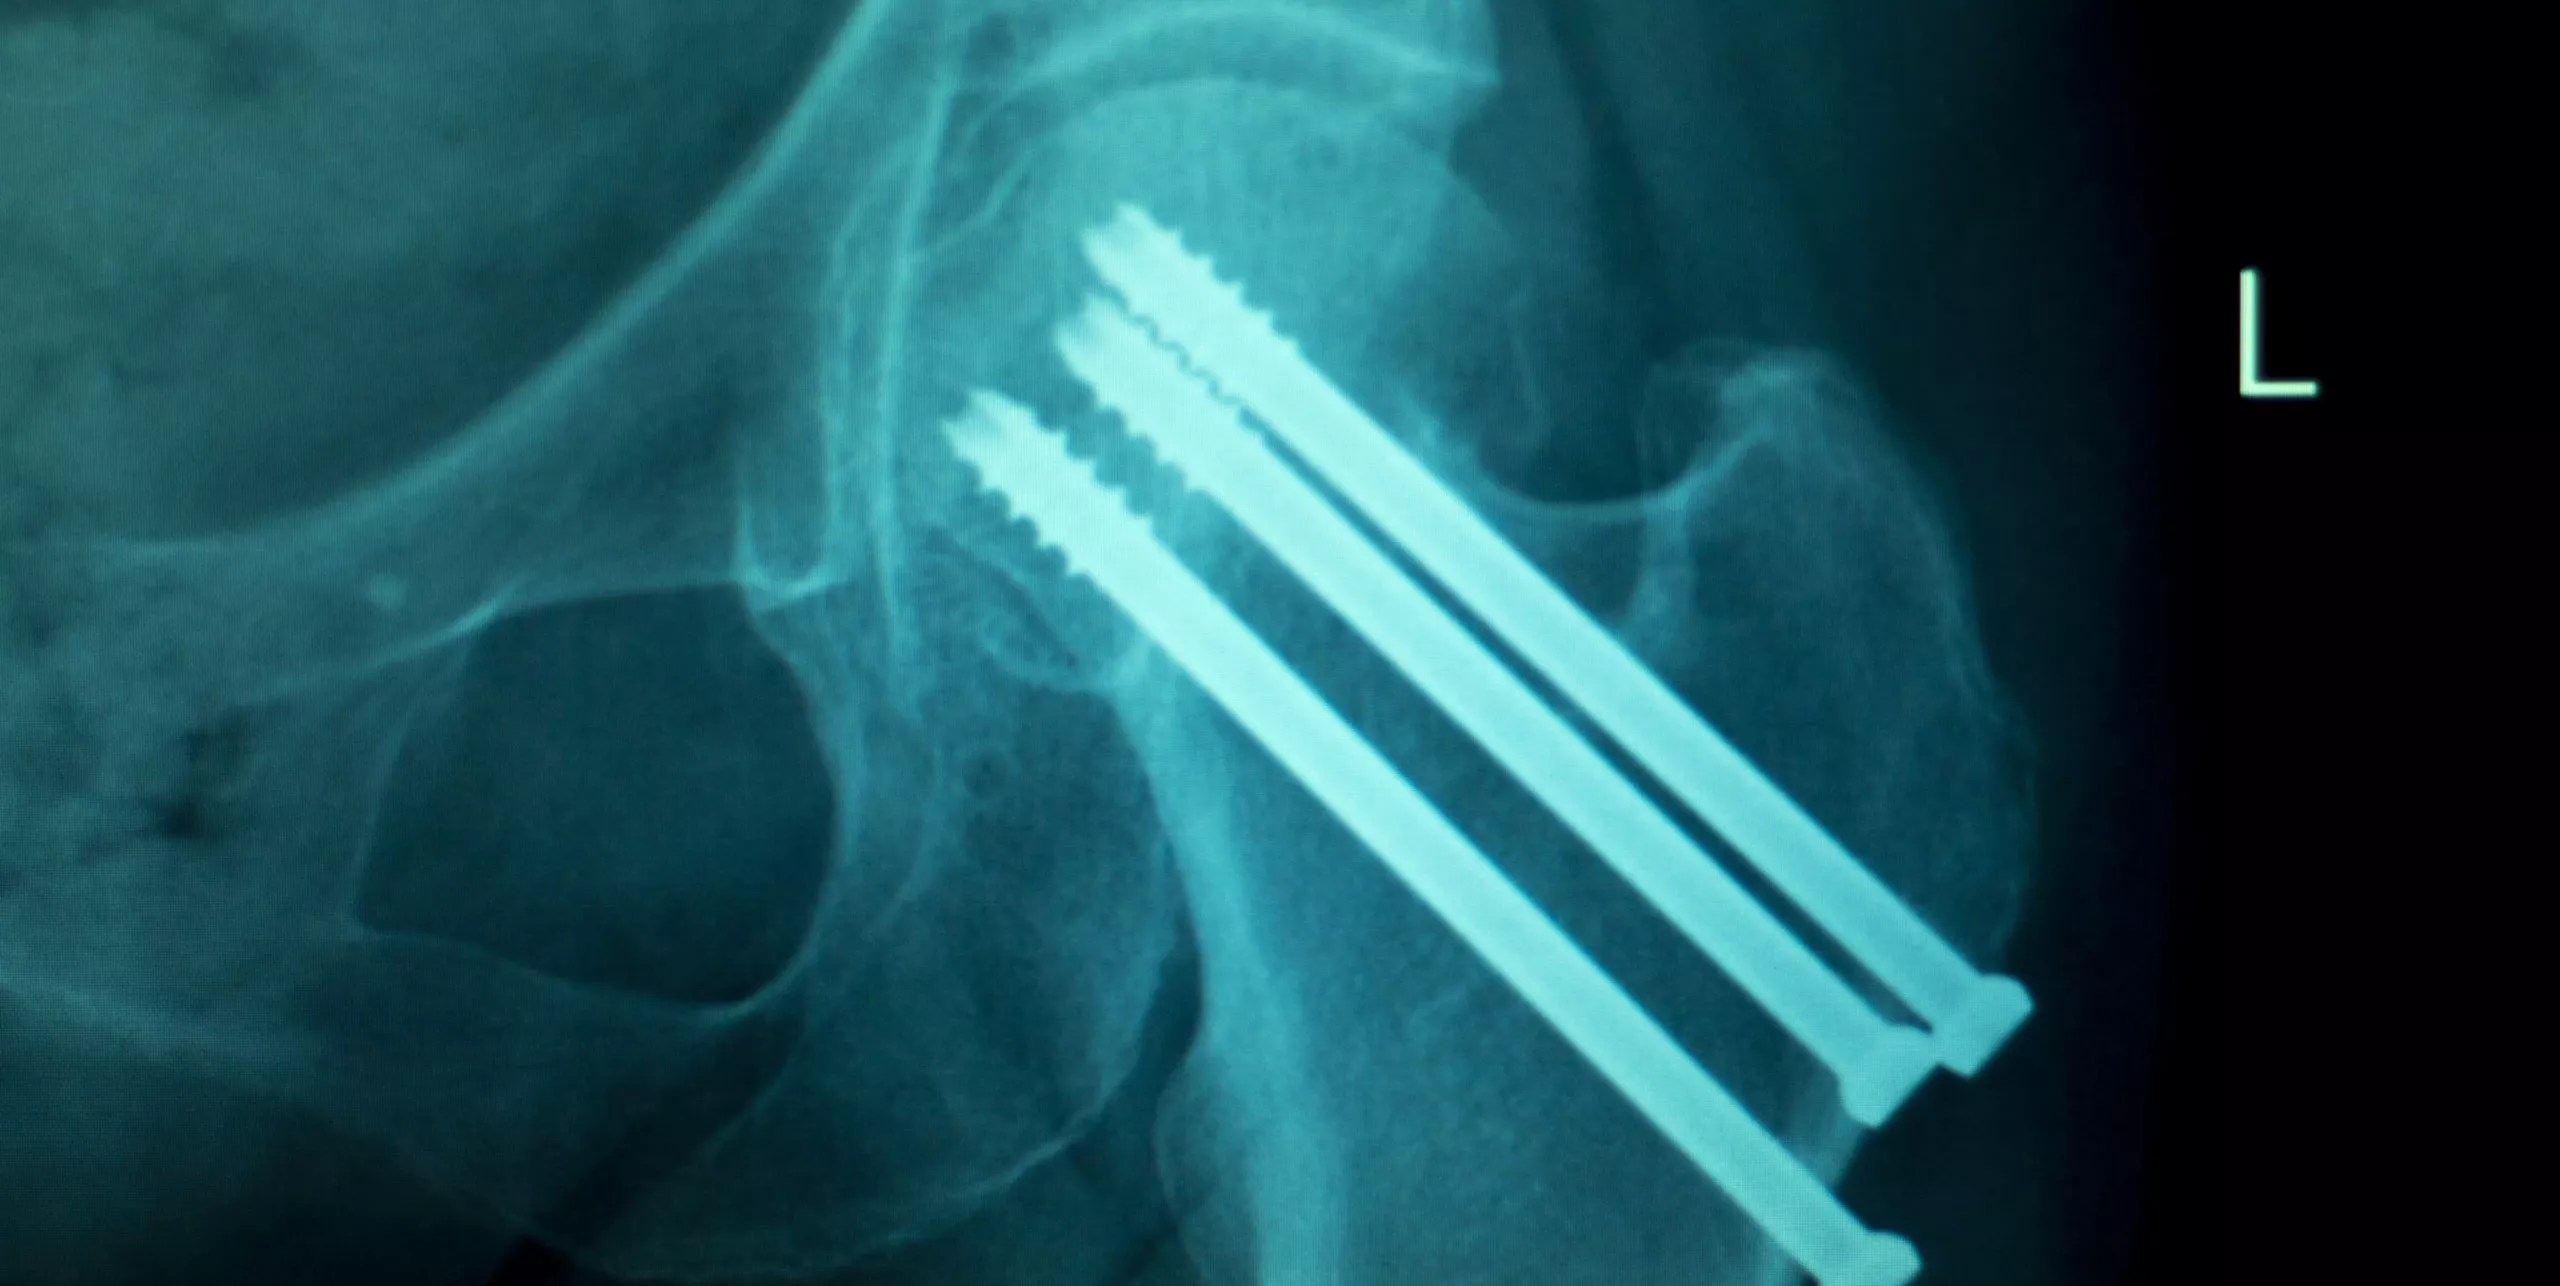

Titanium Screws Side Effects . Long term presence of titanium, or any metal in the body, can sometimes lead to problems. Some of the risks associated with dental implant surgery include: Metal sensitivities and allergies have been implicated in some situations involving pain or problems with orthopedic implants. That said, in most cases having a titanium implant does not present an issue. While the potential for a reaction exists, it's thought to be extremely low. Because of this, surgical fixation devices may eventually need to be removed. There is always a risk with an additional surgery to remove hardware, and the insurance company may not want to pay for it. Pain around the site of orthopedic implants has many causes. Common side effects include localized inflammation, swelling, and pain at the implant site, often due to an immune response. Based on a 2019 review, researchers are investigating the risks of using dental implants made from titanium or other metals.